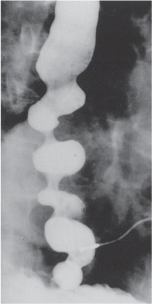

21. A patient with dysphagia undergoes a barium swallow. Based on the image in Fig. 25-12, the most likely diagnosis is

Answer: B

(See Schwartz 9th ed., p 852, and Fig. 25-12.)

FIG. 25-12. Barium esophagogram of patient with diffuse spasm showing the corkscrew deformity.